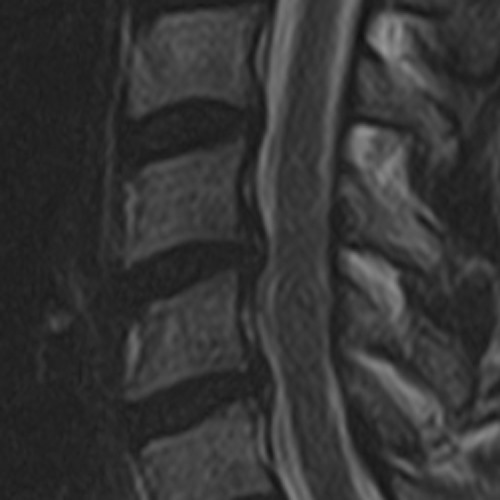

2019, auch da schon leichte Kompression

09112023III

2023, eindeutig keine Verbesserung